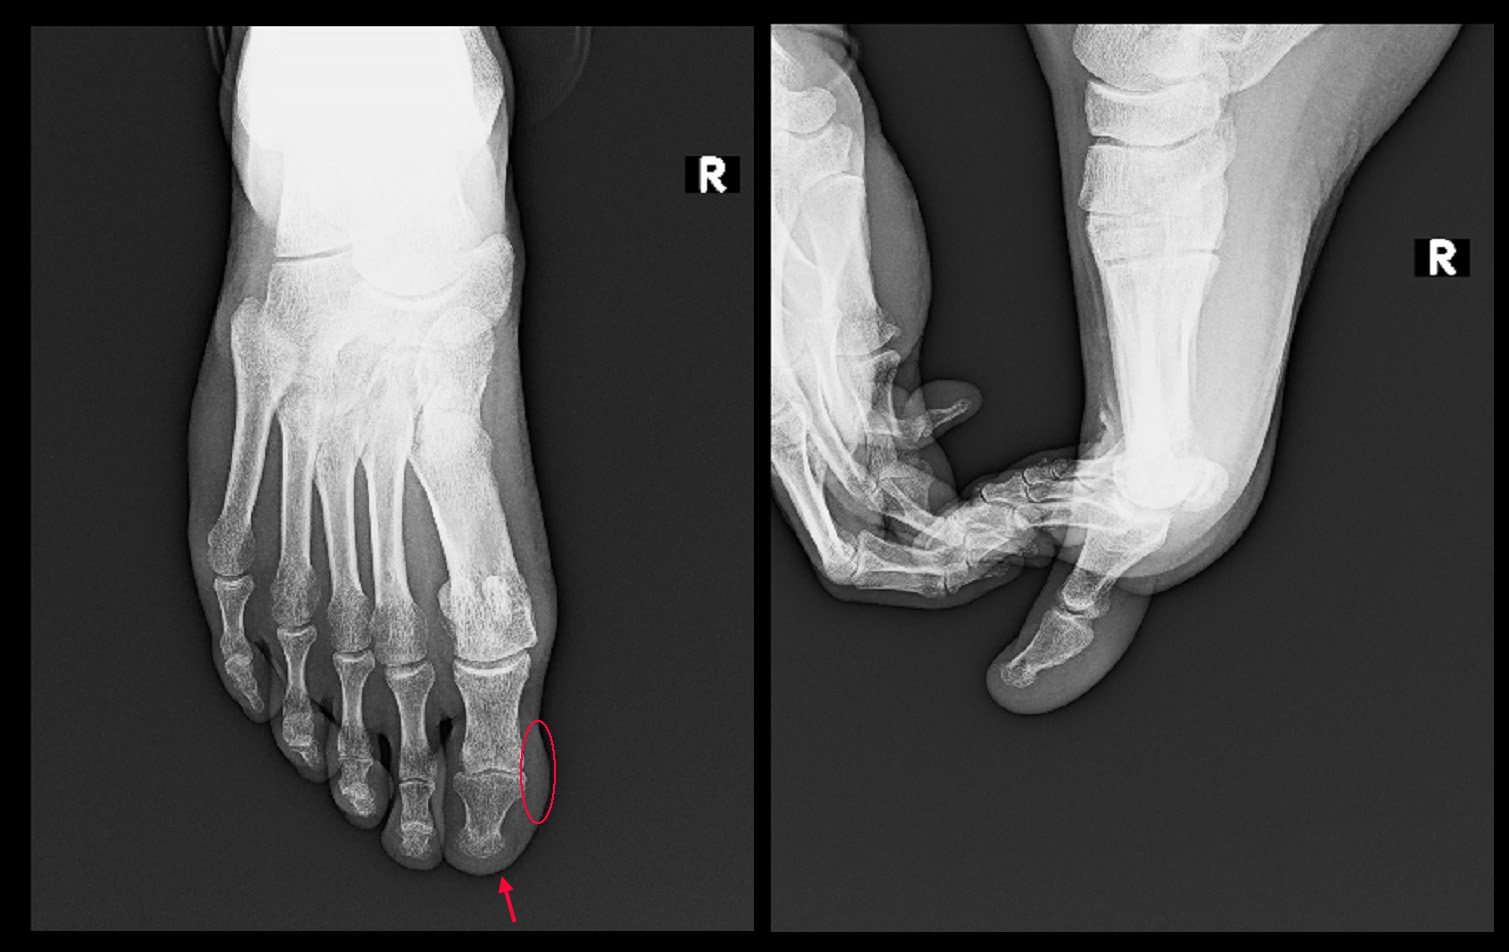

Kさんの足・足指のレントゲンは撮影しておらず、提示するレントゲン像は他の患者さんのものを代用していますが、中央にカルテに記載した図の赤領域が患者さんが針を刺すような痛みを訴えていた部位です。診断上重要なことは左第1足指の痛みの部位に圧痛を認めないということです。圧痛とは局所を押してみて痛みが確認されれば圧痛+で、その局所に痛みの原因があると医師は判断し、押してみて痛みが出なければ、その局所には痛みの原因がないと判断することが多いのです。この患者さんの痛みの領域はごく限定的な領域ですから、そこに痛みを起こす病態があれば必ず圧痛をともなうはずです。例えば巻き爪で爪が皮膚に食い込んで痛みを起こす場合がありますが、その場合には爪の周囲を押せば痛く、患者さんは押されるのを嫌がるものです。トゲが刺さって痛い場合も同様です。しかしKさんの足指には圧痛がないのですから、医師は左第1足指の足先には痛みの原因がないと判断するのです。では、痛みの原因はどこにあるのでしょうか。Kさんは足指の痛みとともに腰痛を訴えています。私は左第1足指の痛みは腰が原因で起きた坐骨神経痛の一症状だと判断しました。このようなことは時々あるものです。

次の患者さんは44才男性のSさんです。令和5年1月13日に当院を受診されました。数年前から右第1足指の内側に感覚の違和感があったとのことですが、最近指先に針で刺すような痛みが出てきたので受診したということでした。赤丸領域が違和感の部位で赤矢印が針刺すような痛みの部位です。